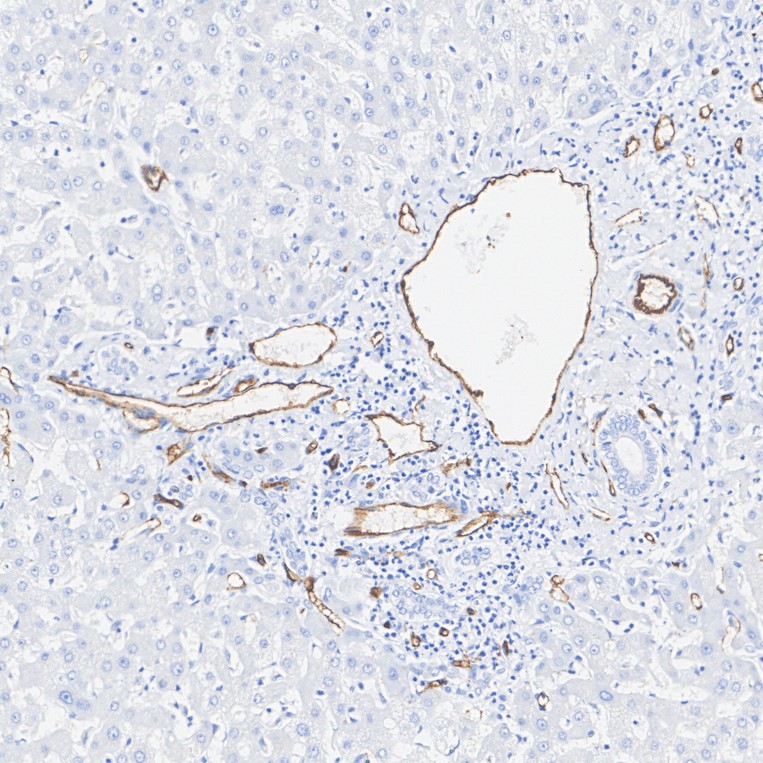

HA601109_1.jpg Fig1: Immunohistochemical analysis of paraffin-embedded human liver tissue with Mouse anti-CD34 antibody (HA601109) at 1/5,000 dilution.

The section was pre-treated using heat mediated antigen retrieval with Tris-EDTA buffer (pH 9.0) for 20 minutes. The tissues were blocked in 1% BSA for 20 minutes at room temperature, washed with ddH2O and PBS, and then probed with the primary antibody (HA601109) at 1/5,000 dilution for 1 hour at room temperature. The detection was performed using an HRP conjugated compact polymer system. DAB was used as the chromogen. Tissues were counterstained with hematoxylin and mounted with DPX.